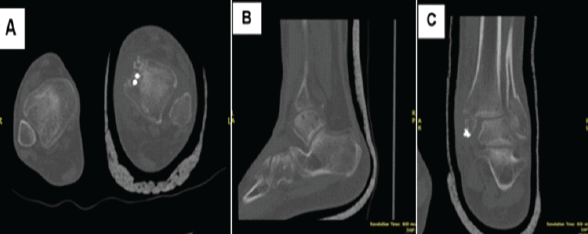

A CT scan showed evidence of a bimalleolar fracture of the left ankle and increased diastasis of the syndesmotic joint, seen using a side-to-side comparison of the tibiofibular clear space with the contralateral side (Fig. 2).

Figure 2: Preoperative axial (a), sagittal (b), and coronal (c) Computed tomography scans of the left ankle showing a bimalleolar ankle fracture and syndesmotic joint injury.